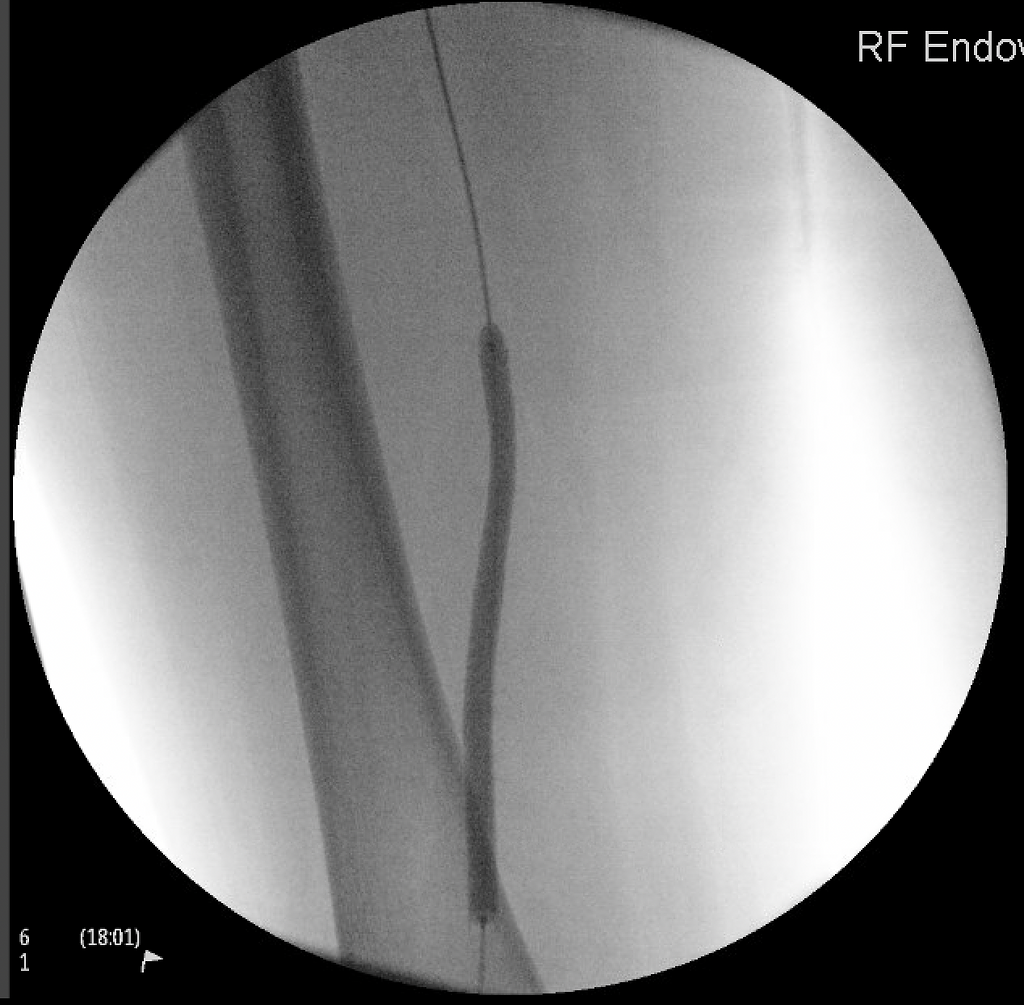

Endovascular treatment for arterial disease utilizes minimally invasive procedures, like angioplasty and stent placement, to restore and support blood flow, providing effective and targeted interventions for improved vascular health.